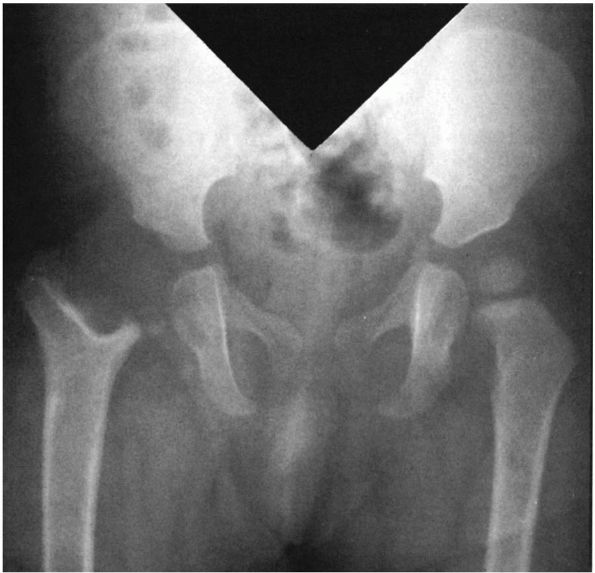

FIGURE 5-3.

AP radiograph of the pelvis of a 1-year-old girl who had an osteomyelitis of the proximal femur and a septic arthritis of the hip as a neonate. These infections resulted in destruction of the physis and the epiphysis. |

itself, producing complete growth arrest (Figure 5-3).

This is most likely to occur in the proximal femur, where the result is

destruction of the head of the femur. The infection frequently spreads

out of the involved epiphysis into the joint, producing a septic

arthritis.